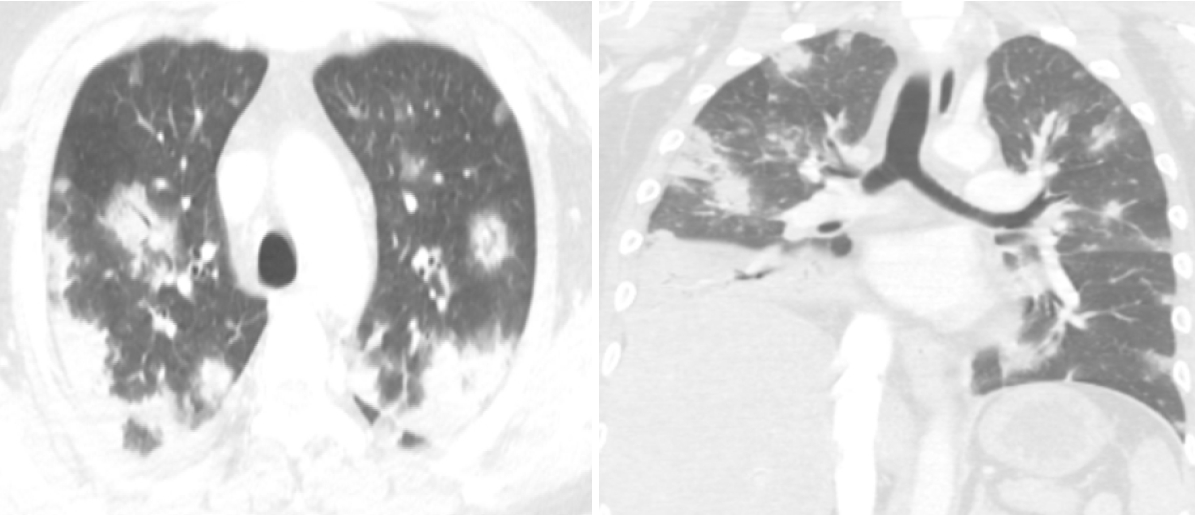

Laboratory findings revealed a white blood cell (WBC) count of 13,500/mm3, hemoglobin 9.5 g/dL, platelet count 207,000/mm3, C-reactive protein (CRP) level 22.91 mg/dL, procalcitonin > 100 ng/mL, blood urea nitrogen 44.7 mg/dL, serum level of creatinine 10.03 mg/dL, total CO2 content 24.4 mmol/L, random blood glucose 719 mg/dL, and hemoglobin A1C 8.0%. Routine urinalysis showed bloody and turbid urine with > 100 red blood cells per high power field (HPF), 31-50 WBCs/HPF, and mild bacteriuria. Initial plain radiography revealed multiple focal opacities in both lung fields and foci of air accumulation behind the pubic ramus. A subsequent abdominal computed tomography (CT) scan displayed multiple air foci in the prostate gland and bilateral seminal vesicles, with thickened urinary bladder walls indicative of emphysematous prostatitis with cystitis (Fig. 1). A chest CT scan demonstrated multifocal consolidations and groundglass opacities, likely due to septic embolic pneumonia (Fig. 2).

Figure 2.

Chest CT obtained upon admission reveals multifocal ground-glass opacities and consolidations in both lung fields, consistent with septic embolic pneumonia. CT, computed tomography.